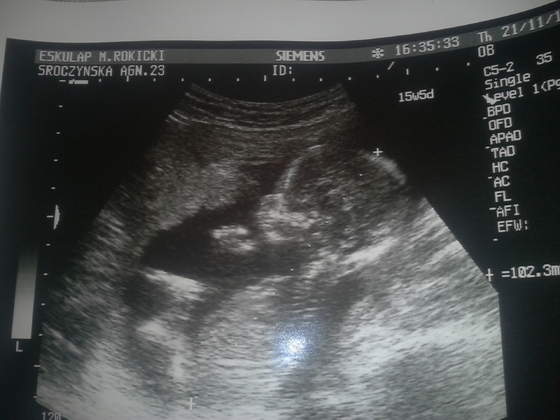

Miałam wczoraj USG:) wszystko ok:):):) dzieciaczek w lekkim wyproście 7cm:) czyli pewno ok 6,5 bez wyprostu;) bardzo ruchliwy bąbel..na 80% chłopiec.Zobacz załącznik 595314Zobacz załącznik 595315Zobacz załącznik 595316Zobacz załącznik 595317

ale wiecie co? liczyłam na córkę;-)

Moj Syneczek <3